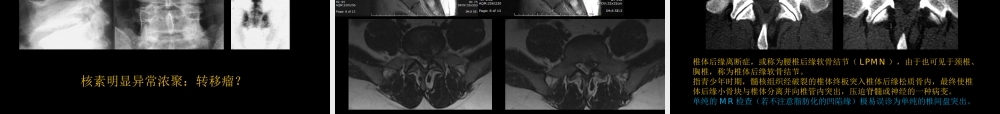

骨关节常见病影像学诊断中国石油中心医院杨景震制作2015内容•骨关节疾病影像检查与诊断概念的更新•影像检查选择与相互补充•常见病影像解读•简述髋关节撞击综合征浅谈骨关节影像学诊断的理念更新•X线时代甚至CT问世后没有听说过的:骨髓水肿,是怎么回事?它在疾病诊断中的意义?(能列举几类疾病吗?)——虽然不特异,却是疾病影像学诊断中敏感的征象•影像检查的多元化,使得对一些疾病的认识,更深入,举几个例子:•髋部疼痛1、炎性疾病(感染、TB、肿瘤、骨关节病……..)2、强直性脊柱炎、类风湿3、股骨头缺血性坏死4、髋臼发育不良3、其他……?一种往往被忽略的一种疾病(撞击综合征)•MRI软组织分辨率高,使得骨-软组织的病变同时显像,信息多(感染、肿瘤、外伤),诊断信任度高。——现今的骨与关节影像与传统的含义不同•计算机的三维重建技术,病变影像直观(类风湿、强脊炎、椎体的退变、绒毛结节性滑膜炎等)——病理的影像特征更丰富。使得经验医学逐渐地弱化。“骨髓水肿”这一词,是随着MRI的应用而出现,即只有做MRI才能发现骨髓水肿的存在,因为MR检查对水很敏感,故显示骨髓水肿具有特征(T2WI压脂上白,在T1WI上黑),并直接可作出诊断。其他影像检查不能够发现或诊断骨髓水肿(包括X线片、CT、PET-CT、超声等)。“”骨髓水肿它只是某些疾病中的表现之一,或某一阶段,并不是独立的疾病。它的出现可见于:骨感染性疾病;骨关节外伤;肿瘤;骨的缺血性疾病;骨关节免疫性疾病;退行性骨关节病;血液疾病;代谢或中毒等。由于感染、损伤、肿瘤、缺血、中毒等病理情况造成病变区骨组织中水成分增多。“骨髓水肿”对疾病的意义:病变处于新鲜性、早期,或者是该病的进展期、活动期。一些“骨髓水肿”随着治疗或疾病转归而消失,提示疾病好转;有的“骨髓水肿”随着病情的进展会加重,比如严重的感染、恶性肿瘤等。关于骨髓水肿Positivecorrelationofbonemarrowedemainhistopathologicalassessmentandmagneticresonanceimaging.(a)Magneticresonanceimaging(T2sequence)ofazygapophysealjointwithbonemarrowedema(cyanarrow).(b)Hematoxylinandeosinstaining,revealingdenseinfiltrationsofmononuclearcells(yellowarrow)andinterstitialbonemarrowedema(redarrow).(ArthritisResTher.2006V8N5)MR的骨髓水肿与病理对照T2WI以AS为例AS的椎小关节水肿MR图(蓝箭)病理图女,31岁膝关节感染T10、11椎体结核骨髓水肿脊椎转移...